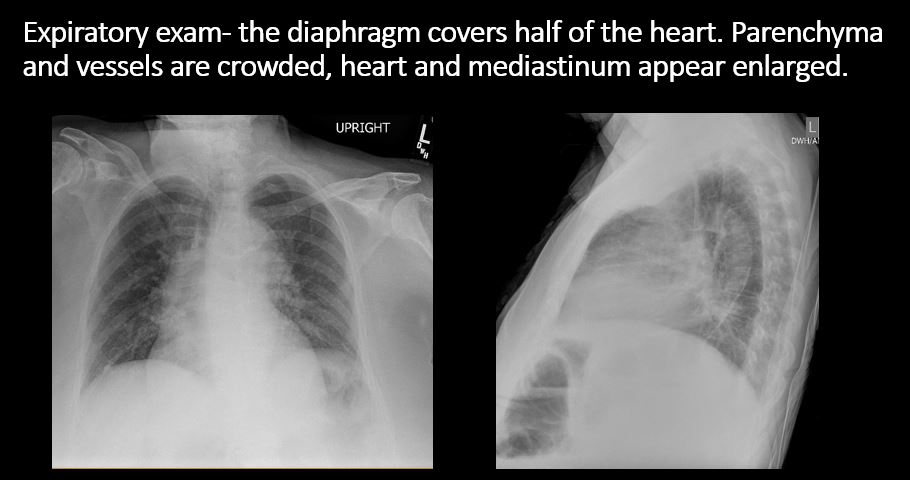

Section 1 Submit Findings Case322 Findings Technique The exam is expiratory, rotated, over or under penetrated, or limited by overlying structures or soft tissues, body habitus, patient positioning, or motion. Yes No Support Devices There is a vascular line or lines present in an abnormal location or otherwise abnormal. Yes No There are other devices such as a chest tube or pleural drain, feeding, NG, or gastrostomy tube, LVAD or pacemaker, vascular stents, cardiac valves, anesthesia catheter, VP shunt, neurostimulator, or other drains or tubes present that are in an abnormal position or are otherwise abnormal. Yes No Cardiomediastinum The superior mediastinum is abnormally widened considering the technique. Yes No There is abnormal shift of the mediastinum. Yes No There is a mass or other abnormal density in or overlying the mediastinum. Yes No There is an abnormality in the retrosternal, retrotracheal, or retrocardiac space on the lateral view. Yes No There is abnormal tracheal deviation or narrowing on the frontal and/or lateral view. Yes No There is pneumomediastinum and/or pneumopericardium. Yes No There is enlargement of the cardiac silhouette. Yes No The heart borders are abnormal. Yes No The right paratracheal stripe is thickened or enlarged. Yes No The azygoesophageal recess is displaced or otherwise obscured. Yes No Vasculature and Hila The aorta is dilated, tortuous, ectatic, calcified, or there is a focal contour abnormality. Yes No The central pulmonary arteries or hila are enlarged. Yes No The aorto-pulmonary window is convex or obscured by a mass, adenopathy, or vasculature. Yes No There is cephalization or haziness of the pulmonary vessels or congestion of the central pulmonary vasculature. Yes No Lungs The lungs are hyperinflated or underinflated generally or segmentally. Yes No There is focal, multifocal, or diffuse airspace disease, mass, opacity, or nodularity. Yes No There is focal or diffuse interstitial disease. Yes No There is focal or lobar atelectasis or total collapse of the lung. Yes No There is cavitary or cystic disease with or without air fluid levels or soft tissue nodularity. Yes No The position of the major and minor fissures is abnormal. Yes No The right or left hemidiaphragm is focally or diffusely obscured on the frontal and/or lateral view. Yes No There is elevation, depression, or contour abnormality of the right or left hemidiaphragm. Yes No Pleura There is focal or diffuse abnormality of the pleura or chest wall. Yes No There is a pleural effusion, blunting of the costophrenic angle, or posterior sulci. Yes No There is focal fluid in the fissures. Yes No There is asymmetric pleural thickening or capping of the apices. Yes No There is a pneumothorax, hydro/pneumothorax, or hemo/pneumothorax. Yes No Bones, Soft Tissues, Upper Abdomen The ribs, clavicles, shoulder, spine, or other visualized bones are abnormal. Yes No There is free air beneath the diaphragm. Yes No The bowel or organs of the upper abdomen are abnormal. Yes No There is subcutaneous emphysema, focal or diffuse soft tissue abnormality, radiopaque foreign body, or post-surgical change or hardware. Yes No